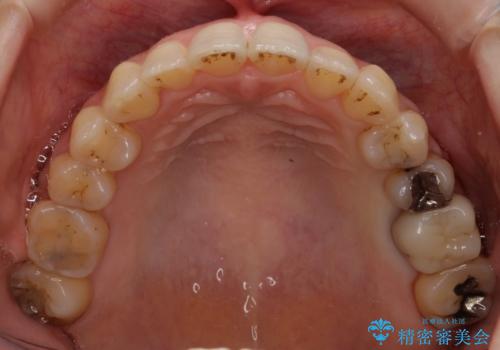

- 前歯のガタガタを主訴に来院。

前歯は開咬傾向であり、小臼歯から大臼歯にかけてもオーバージェットは非常に小さく咬耗していました。

非抜歯で前歯の重なりを作るのは難しいとご説明しましたが、インビザラインでできるところまで並べていくことになりました。

結果、非常に真面目に治療に取り組んでいただき、期間はかかりましたが予想以上の結果を得ることができました。

途中再評価を行い、矯正用のミニスクリューを用いて奥歯を遠心移動し、前歯の出っ歯傾向を改善しました。

左上12の段差についてはここまで直すのにもかなり時間がかかりました。インビザライン単独では限界があると説明し、ワイヤーの部分矯正もご提案しましたが、患者様のご希望によりインビザラインでできるところまで頑張るということで4回ほどリファインメントを行いました。